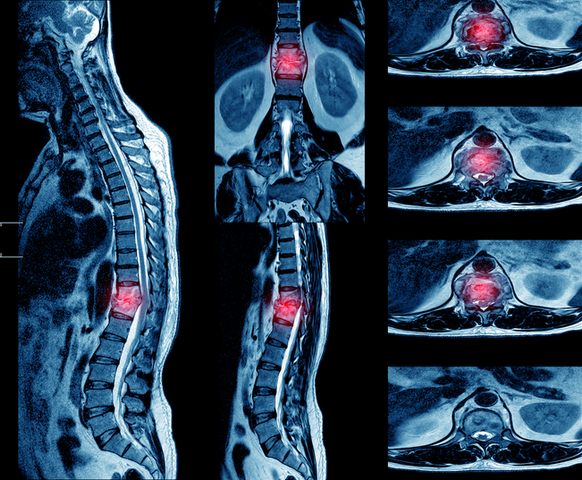

תופעה זו אופיינית ברוב המקרים לבני 60 ומעלה ובה התעלה בעמוד השדרה צרה מידי בכדי להכיל באופן נוח את חוט השדרה. צרות התעלה מייצרת לחץ על חוט השדרה ומכאן מובילה לכאבים משמעותיים בגב התחתון, לצד כאבים וזרמים ברגליים ואף למגבלה משמעותית ביכולת ללכת ולעמוד.

הסיבות להיצרות תעלת עמוד השדרה יכולים לקרות עקב פציעת ספורט או תאונה, פגיעה בחוליות או במפרקים שמהם נוצרים בלטים המייצרים לחץ על עמוד השדרה, תזוזה של חוליות, שינויים מולדים ותורשתיים ואף גידולים שפירים בתעלה עצמה.